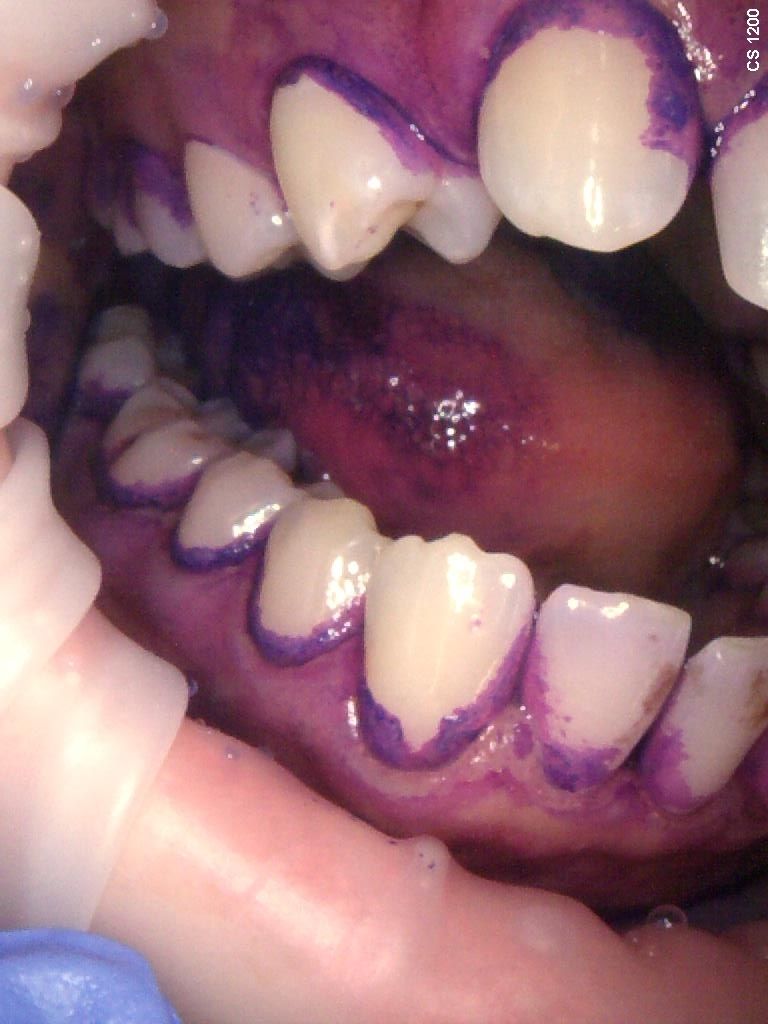

Zdjęcia i filmy

• Fluoryzacja zębów

• Pakiet higienizacyjny

• Pakiet higienizacyjny z instruktażem

• Piaskowanie